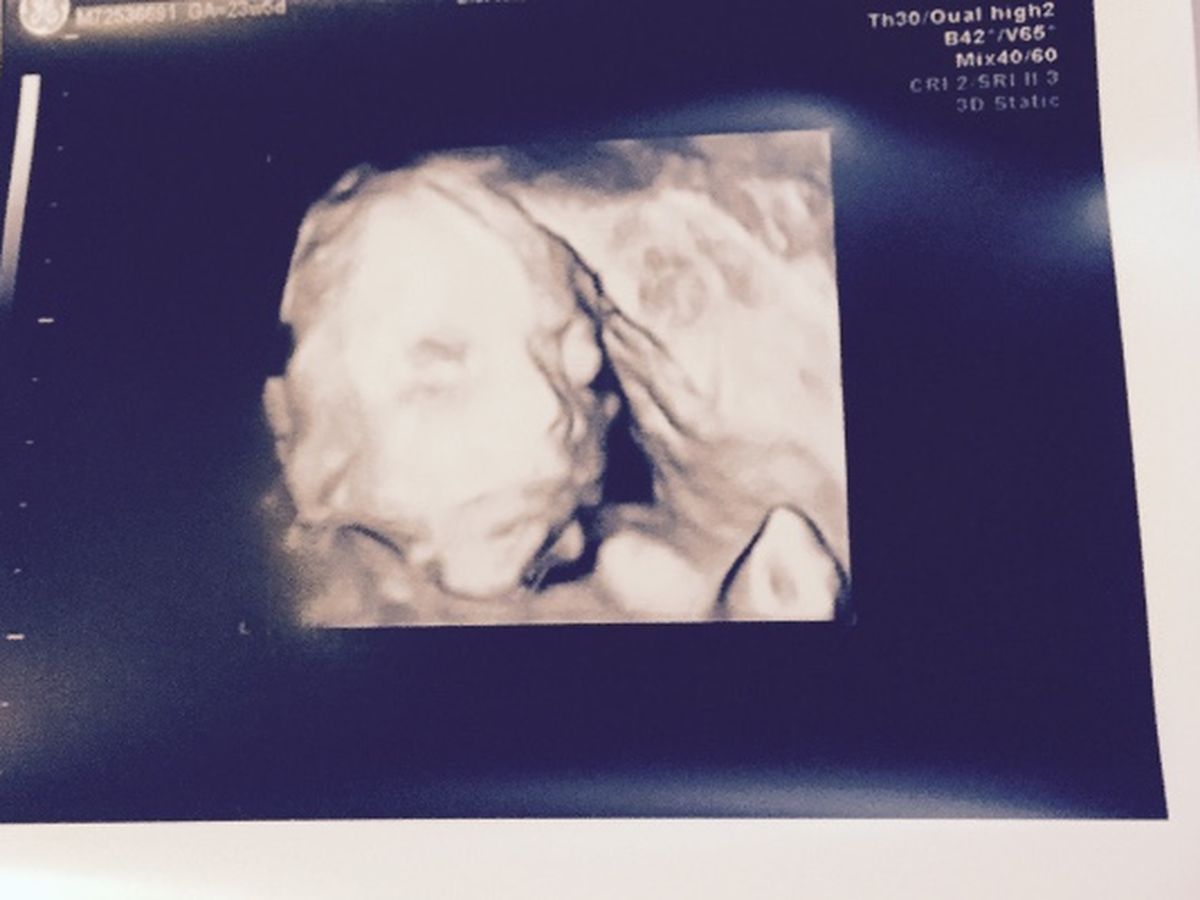

Jase's Journey is going to be long and hard, but we aren't going to give up. On June 7th Henry & I told our immediate family that we were expecting a baby boy, our 4th child, and shortly after we found out our miracle has a single ventricle heart and will need several open heart surgeries after he is born.. We will fight for his broken heart, and for his life, and we are asking for a little help from family & friends if you are able to. Thank you in advance!